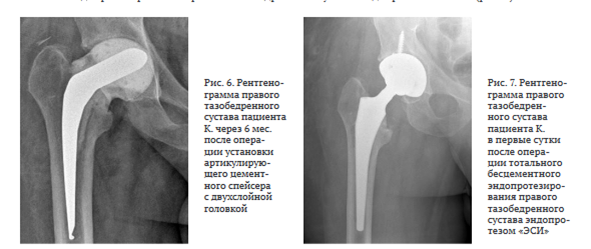

Повторно госпитализирован через шесть месяцев. Местный статус: укорочения правой нижней конечности нет. Послеоперационный рубец — без признаков воспаления.

Функциональные показатели сустава по шкале HHS — 77, по шкале WOMAC — 24, выраженность болевого синдрома по шкале ВАШ — 2 балла. При пальпации обнаружена незначительная локальная болезненность в проекции правого тазобедренного сустава (2 балла по шкале ВАШ).

Рентгенограмма представлена на рис. 6.

Выполнена пункция периимплантного пространства из трех точек. При микробиологическом исследовании операционного материала роста микрофлоры не выявлено.

10.10.2023 произведена операция в объеме: удаление артикулирующего спейсера, тотальное бесцементное эндопротезирование правого тазобедренного сустава эндопротезом «ЭСИ» (рис. 7).

Через 12 мес. после второго этапа эндопротезирования в объеме удаления артикулирующего спейсера, тотального бесцементного эндопротезирования левого тазобедренного сустава Beijing Montagne Medical device / Zimmer функциональные показатели сустава пациента по шкале HHS — 89, по шкале WOMAC — 14, выраженность болевого синдрома по шкале ВАШ — 1 балл. Рентгенограмма представлена на рис. 8.

Через 12 мес. после операции тотального бесцементного эндопротезирования правого тазобедренного сустава эндопротезом "ЭСИ" функциональные показатели сустава по шкале HHS — 91, по шкале WOMAC — 11, выраженность болевого синдрома по шкале ВАШ — 0 баллов. Рентгенограмма представлена на рис. 9.